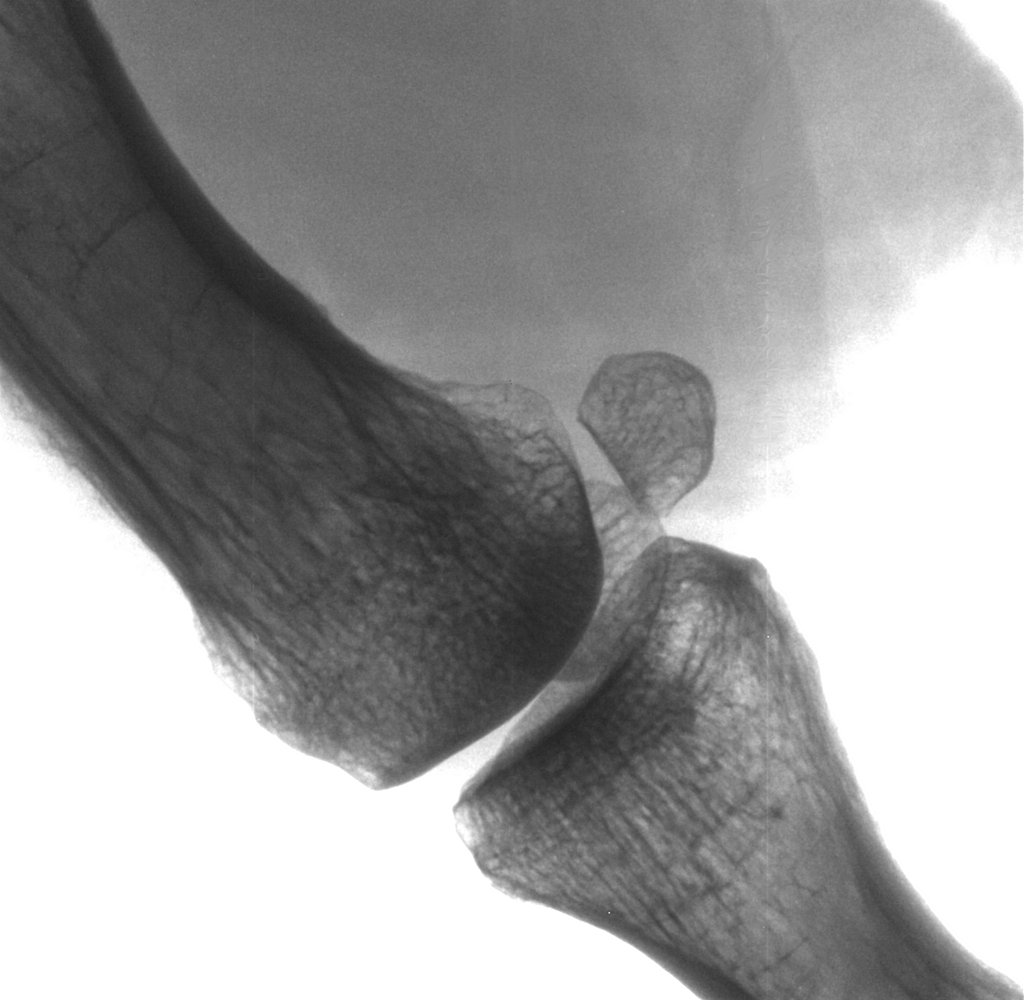

Daumengelenk (40kV/0.2mA).